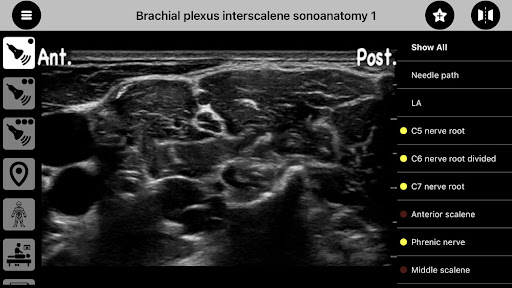

Been using AnSo Anaesthesia Sonoanatomy for a couple months now. It’s basically an app that helps anaesthetists identify common sonoanatomy and understand the surrounding structures. Basically a useful tool for doctors working in the operating theatre.

There’s a bunch of features – you can see examples of different sonoanatomy, which is great for learning pattern recognition. It’s got some sketches too that show the landmarks, which is handy for exams. And there’s even a bunch of different views of the same anatomy, since everyone’s body is a little different.

So here's my take on AnSo Anaesthesia Sonoanatomy. I've tested a bunch of medical reference apps and this one's pretty solid. The content is really comprehensive and the visuals are clear. Definitely helps you understand the sonoanatomy better than just reading a textbook. But the UI is a little outdated and it can be tricky to navigate at first. Overall though, it's a useful tool if you're learning ultrasound-guided procedures.